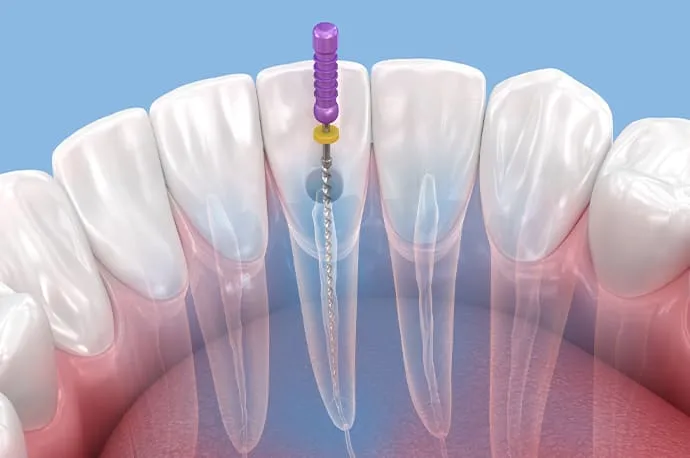

①根管拡大

ニッケルチタンロータリーファイルを使用し、根管を適切な形に広げながら、内部に存在する細菌を物理的に取り除いていきます。

根管の長さの測定

根管口が見つかったら、ファイルと呼ばれる細い針金のような器具を根の先まで挿入し、根管の正確な長さを測定します。この工程が、治療の精度を左右する重要なポイントになります。

根管の清掃・消毒

測定した長さに合わせて、柔軟性のあるニッケルチタンファイルで根管を最小限に広げます。同時に消毒剤を使用し、根管内部を徹底的に洗浄・消毒していきます。

根管貼薬(1回目治療終了)

ある程度消毒が完了した段階で、根管内にお薬を入れてフタをします(根管貼薬)。この状態で一度治療を終え、1~2週間ほどお薬を効かせます。